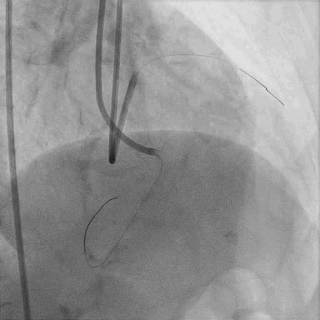

双腔微导管辅助下,导丝在逆向造影指引下成功通过LAD闭塞段,逆向造影显示导丝走行于LAD真腔内

交换工作导丝至LAD远端

预扩球囊依次扩张LAD近中段病变处,造影可见远端血管显影,导丝位于真腔。

于LAD近中段植入Tivoli 2.75*33mm支架一枚,高压球囊后扩张后,血流TIMI3级